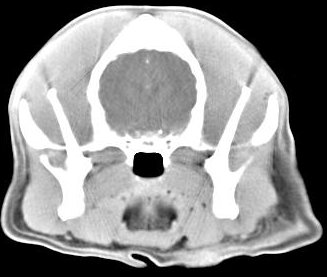

imágenes de TC en el perro | ||||||||||

ejemplo de imágenes de TC en el perro. Nótese la celulitis en la región parotídea izquierda | ||||||||||

Tomografía computarizada helicoidal |